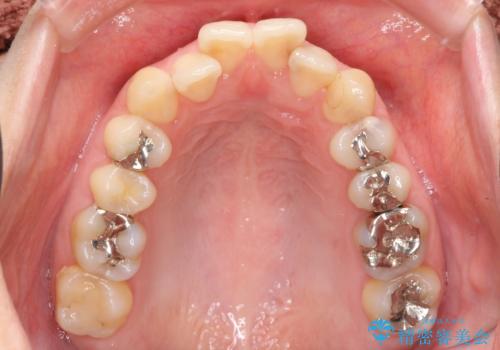

- 前歯2本が後ろに引っ込んでいる状態でした。

マウスピースで歯を抜かずに矯正しました。

かみしめがある方は、奥歯のかみ合わせが弱くなることがマウスピース矯正の欠点ですが、装着時間や時間帯を工夫して奥歯もしっかりかんだ状態で矯正終了をしています。

左上4番は、虫歯治療をして、セラミッククラウンで修復しています。